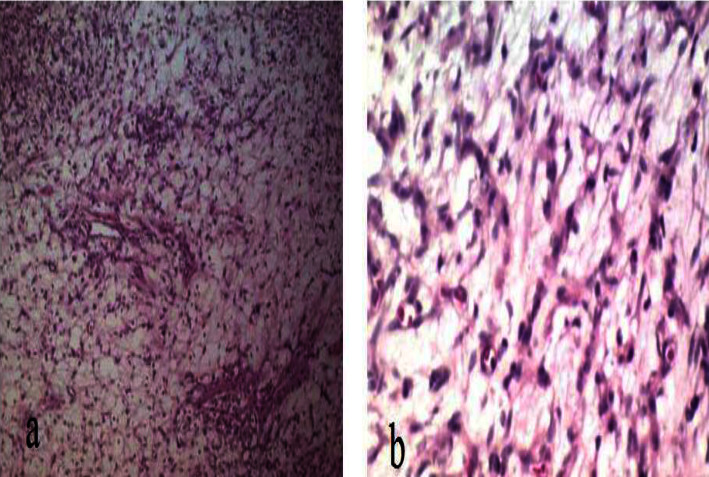

Introduction: Different subtypes of cardiac tumors containing spindle cells have been described as cardiac sarcoma. However, benign types have not been reported so far. We described a neonate with progressive respiratory distress who had a PDA and was finally diagnosed with a right atrial spindle cell tumor. Case Presentation: The patient was a neonate referred with respiratory distress and sepsis. The initial echocardiography demonstrated a small atrial septal defect, patent ductus arteriosus, and a heterogeneous rounded right atrial mass lesion. Pathologic examination confirmed the right atrial myxoid spindle cell tumor without local invasion. Successful mass resection was performed, and follow-up echocardiography revealed normal cardiac structure and function. Conclusion: In infants with manifestations of possible cardiac anomalies, it is necessary to consider other pathologies, such as neoplastic processes. Spindle cell detection in pathology is not ominous all the time, and there are benign subtypes with favorable outcomes after successful surgical resection.